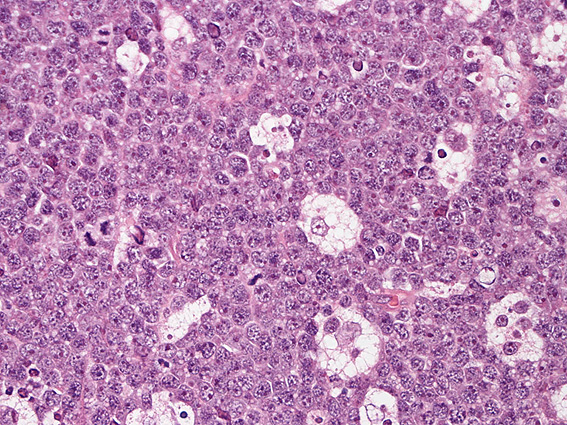

Fig. 1 and 2: 典型的なBurkitt lymphomaの症例(小児腹部腫瘤)

cohesive(凝集した, 密接した), ぎゅうぎゅう詰めの状態で, 中型サイズ[免疫芽球や大細胞リンパ腫の核よりは小さめ]の類円型核をもつリンパ球様細胞が増殖する。核のクロマチンは顆粒状で核全体に分散し, 複数個の核小体を有する。淡明で豊かな胞体のtindible body macrophageがこのcohesiveなリンパ球増殖の中に散在して, 特徴のあるstarry-sky(きらめく星空)パターンを演出している。

macrophageは細胞質内に核片や変性した細胞を貪食する。 増殖細胞には核分裂像やapoptotic changeが多く認められ, turn overの早い, 増殖能の高い腫瘍であることが推察されます。